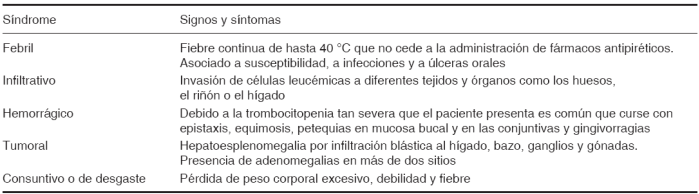

La leucemia es el trastorno oncológico más común de la infancia caracterizado por una afección de la médula ósea que origina una producción excesiva de células inmaduras denominadas blastos. Las leucemias cuentan con una gran pluralidad de características para poder ser clasificadas con base en el tipo celular que las produce o el grado de maduración de éstas.

De acuerdo con los estirpes celulares que las producen, las leucemias pueden ser linfoblásticas o mieloblásticas.1

Las leucemias linfoblásticas son aquéllas cuya celularidad deriva del estirpe linfoide, es decir, linfocitos B y T respectivamente. Mientras que las leucemias mieloblásticas derivan de las células del estirpe mieloide como los glóbulos rojos, neutrófilos, basófilos, eosinófilos y plaquetas (Figura 1). Así se diferencian entre agudas y crónicas de acuerdo con la funcionalidad de las células. Las leucemias agudas se caracterizan por tener una población celular no funcional al estar absolutamente inmaduras a diferencia de las leucemias crónicas en donde las células tienen un mayor grado de maduración. A partir de esta premisa podemos inferir que las leucemias agudas generalmente son más agresivas que las crónicas. El origen de este padecimiento se asocia fuertemente a factores genéticos como el síndrome de Down,2 síndrome de Li-fraumeni, síndrome de Klinefelter, enfermedad de Wiskott Aldrich, anemia de Fanconi, la exposición a radiaciones ionizantes, a agentes químicos en edades tempranas y a una predisposición citogenética específica como la presencia del cromosoma Filadelfia.1,2

Figura 1 Imagen que muestra las células que derivan del estirpe linfoide y el estirpe mieloide en condiciones de salud.

Las leucemias pertenecen al grupo de enfermedades proliferativas malignas. Éstas son de los trastornos oncológicos más comunes en la infancia, además del retinoblastoma, el osteosarcoma y el neuroblastoma.3 Como ya se mencionó con anterioridad las leucemias pueden clasificarse de acuerdo al estirpe celular que las produce y al grado de diferenciación y funcionalidad de las células.1-3

De acuerdo con estudios estadísticos realizados en el 2001 por la Secretaría de Salud en México se registraron alrededor de 13,558 pacientes que fueron ingresados a los hospitales con el diagnóstico de leucemia, de los cuales murieron 232 en un grupo de edad de 1 a 4 años y 558 en el grupo de edad de 5 a 14 años.4,5 La leucemia linfoblástica aguda se caracteriza por aparecer en la primera década de vida; sin embargo, es posible que su frecuencia pueda incrementarse también en pacientes de la tercera edad. Las células inmaduras que en condiciones normales se diferenciarían a cualquier célula del estirpe linfoide o mieloide se le denomina blasto,6 estas células al ser no funcionales no deberían encontrarse en la circulación sanguínea; sin embargo, cuando el paciente debuta con leucemia aparece una producción excesiva de blastos que invaden la médula ósea y por ende, la circulación general. Al producirse una gran cantidad de células inmaduras, éstas ocupan un espacio amplio dentro de la médula ósea de los huesos largos, impidiendo así que las otras células bien diferenciadas puedan reproducirse de forma normal y ocupar su espacio dentro de la médula ósea, generando entonces en el paciente una disminución de todos los conteos celulares (pancitopenia) y además dolor en las extremidades superiores e inferiores. Al tener un descenso importante en el conteo de la hemoglobina y de las plaquetas el paciente cursa con anemia y trombocitopenia que se traduce clínicamente en palidez generalizada, astenia, adinamia y lesiones vasculares en la piel y en la mucosa bucal.5-7 Todo paciente que debuta con leucemia cursa por determinados síndromes asociados, a saber: febril, infiltrativo, hemorrágico, anémico, tumoral y consuntivo (Cuadro I).